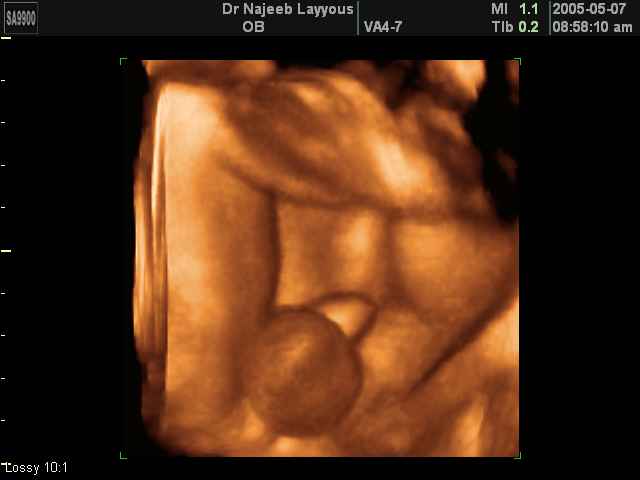

- 3D Photos échographie des parties du fœtus